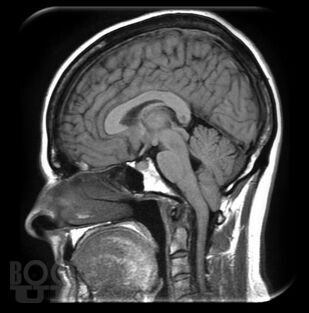

Аномалия Арнольда-Киари

В нем освещены вопросы патогенеза, современные принципы диагностики, лечебные тактики и клинические исследования пациентов с аномалией Арнольда-Киари. Пособие снабжено тестовыми заданиями и ситуационными задачами с эталонами ответов. Предназначено для обучающихся по программе ординатуры по специальности 31.08.56 Нейрохирургия.